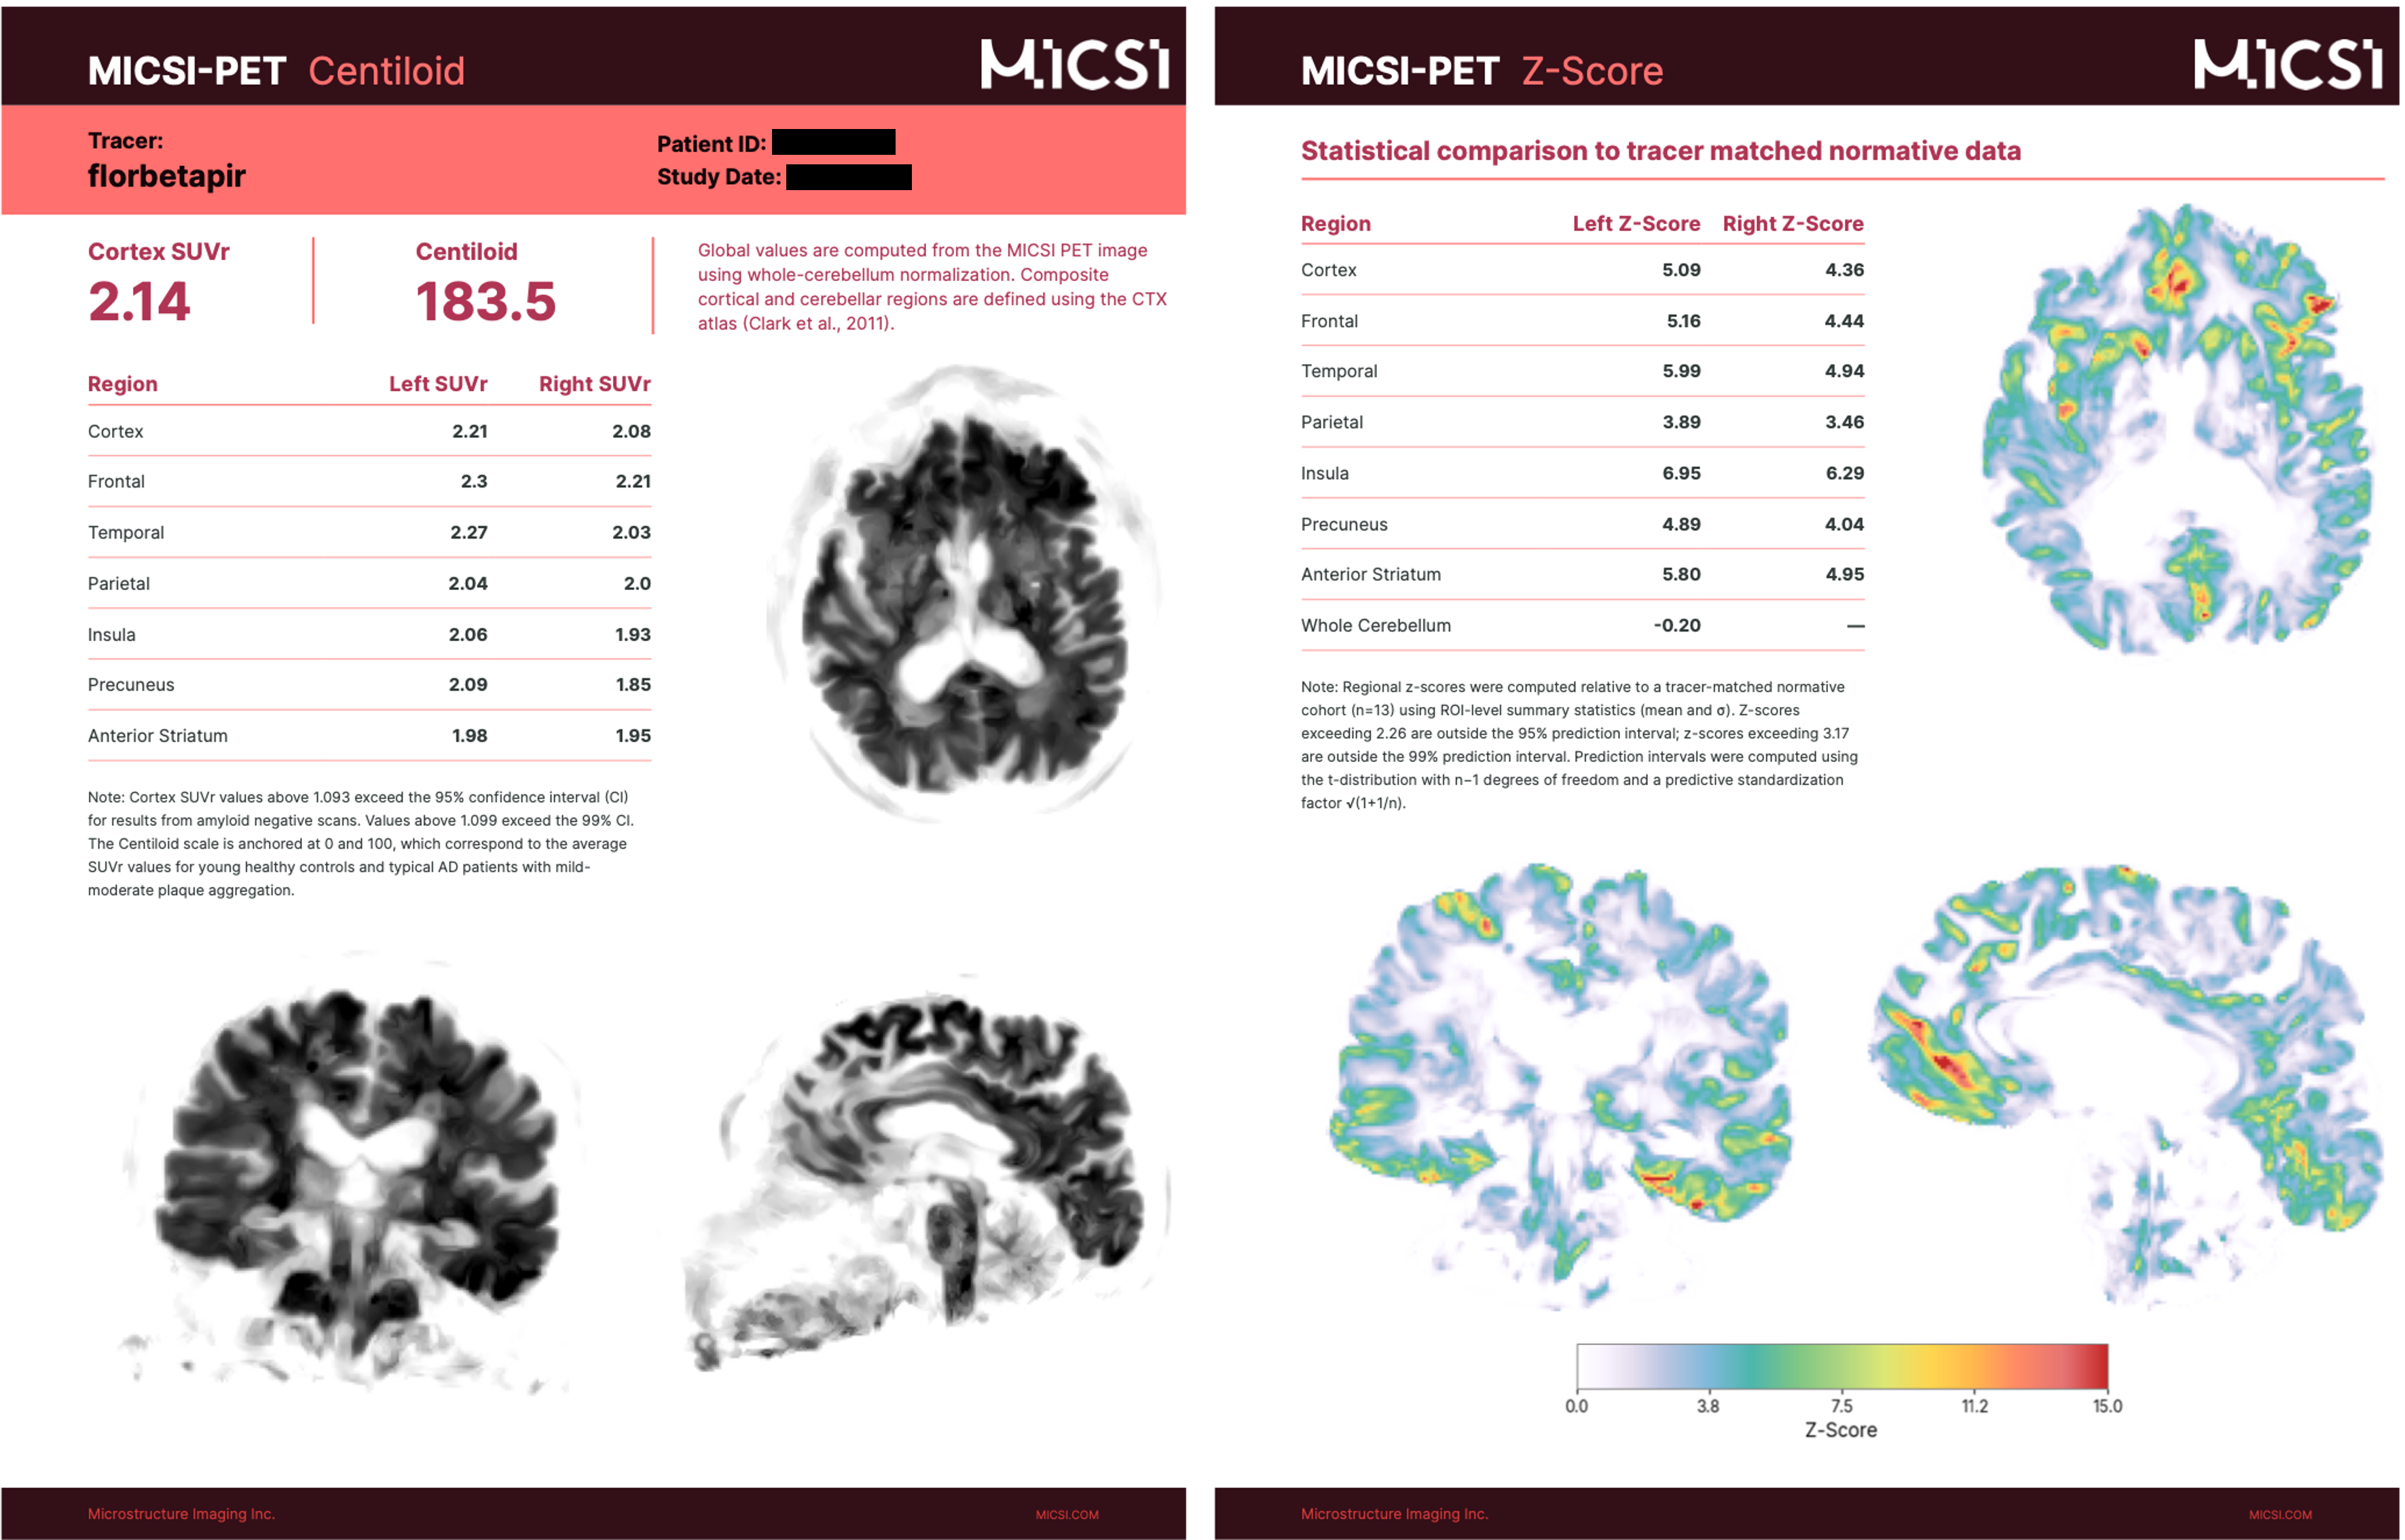

Figure: Coregistered conventional PET and MICSI-PET amyloid images across a range of amyloid burdens, highlighting differences in apparent cortical sparing: left, amyloid-negative with strong gray/white contrast; right, amyloid-positive with reduced gray/white contrast.

Beyond anatomical PET, MICSI-PET is designed to streamline diagnosis through automatic SUVR/Centiloid reporting with built-in QC.